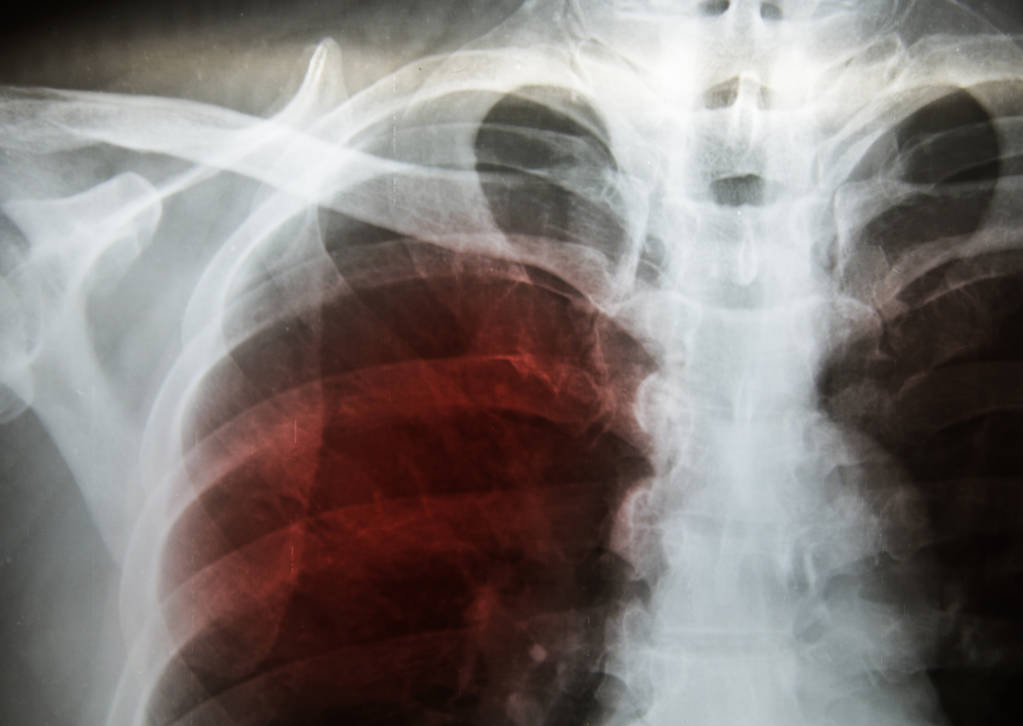

其实 , 激素在我们疾病诊治中的作用还不止上面所说的 , 我们大部分疾病归根到底还是自身免疫力出了问题 , 尤其是肺部疾病 , 很多既不是感染 , 又找不到原因的疾病 , 找来找去还是免疫问题 , 免疫出了乱子 , 会引起肺部各种各样的炎症反应 , 尽出一些奇奇怪怪的毛病 。 这些问题最终靠激素解决或者激素参与解决 , 细数下来 , 一半的肺病会用到激素 , 下面我们来梳理一下 。慢性阻塞性肺病